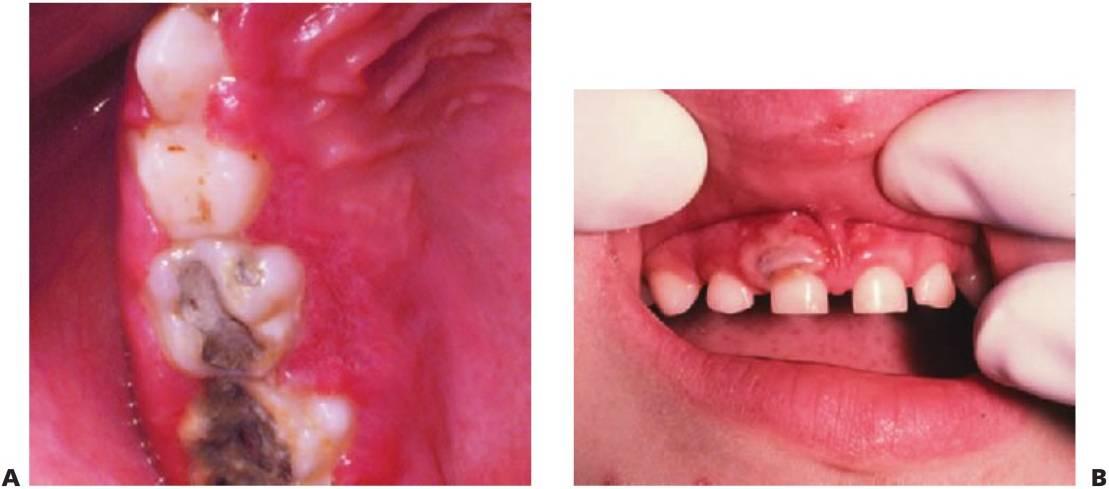

Las infecciones de la fosa canina del maxilar suelen producirse por grampositivos o bacterias anaerobias facultativas (fig. 8.1 A), pero pueden diagnosticarse de forma errónea como una celulitis periorbitaria, que se suele producir por Haemophilus influenzae o Staphylococcus aureus de diseminación hemática. La diseminación posterior puede llevar a una trombosis del seno cavernoso y a un absceso cerebral.

- Drenaje de pus. Si se ha retrasado el diagnóstico del tratamiento adecuado de una infección en la mandíbula y la inflamación ha cruzado la línea media, o bien existe una inflamación en el suelo de la boca, se debe considerar la realización de un drenaje extraoral de entrada-salida (fig. 8.1B, C). Si se eleva un colgajo, se debe eliminar todo el tejido de granulación e irrigar la zona minuciosamente. Los colgajos han de aposicionarse y suturarse sin ejercer mucha tensión con las suturas. Por último, los niños toleran mejor los drenajes flexibles blandos que los tubos corrugados.